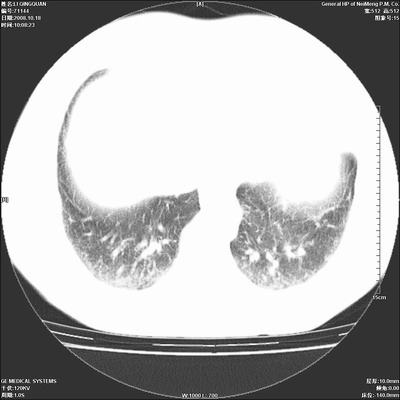

以下是引用duguo在2008-10-19 13:59:00的发言:[br]左肺上叶支气管狭窄,首先考虑中心型肺癌伴阻塞性肺炎\\肺不张.

以下是引用ybing在2008-10-19 12:58:00的发言:[br]左肺上叶阻塞性炎症-建议支气管镜进一步检查除外中央型肺癌

以下是引用随光逐影在2008-10-19 14:31:00的发言:[br]考虑左肺中央型肺癌并左肺上叶阻塞性肺炎,肺不张。